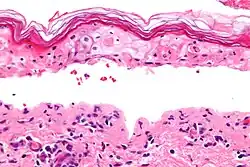

| Micrograph of confluent epidermal necrosis. H&E stain. | |

In dermatology, erythema multiforme major is a form of rash with skin loss or epidermal detachment.

The term "erythema multiforme majus" is sometimes used to imply a bullous (blistering) presentation.[2]

In this view, EM major, SJS and TEN are considered a single condition, distinguished by degree of epidermal detachment.[3][4]

However, a consensus classification separates erythema multiforme minor, erythema multiforme major, and SJS/TEN as three separate entities.[3]